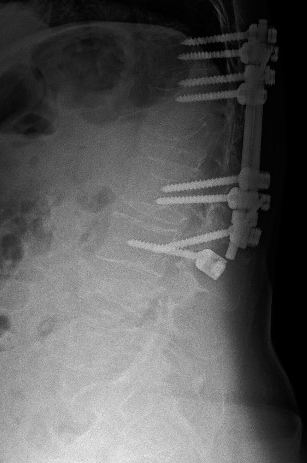

Yapılmış olan MRG incelemesinde L4 vertebrasında yeni kırık görülüyordu. Yaptırılan direkt grafi ve BT incelemelerinde ise daha önce yapılmış olan T11-L3 stabilizasyon sisteminin alt uçta gevşeyerek disfonksiyone olduğu saptandı.

Direkt grafi AP görüntüsü - İmplant yetmezliği Direkt grafi lateral görüntüsü - L4 kırığı

Resim 2: Direkt grafilerde L4 vertebrasındaki kırık yanında, eski bir L1 kırığı nedeniyle yerleştirilmiş olan T11-L3 transpediküler vida sisteminin disfonksiyone olduğu görülüyor. L3 vidasında sağ tarafta muhtemelen gevşemeye bağlı vida çıkması, solda ise vida başının roddan kurtulduğu görülüyor.